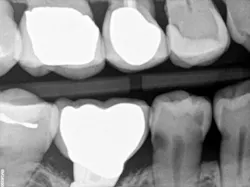

When decay arises on adjacent teeth, dentists must evaluate their treatment options. I have found there is a high degree of difficulty restoring large Class II or interproximal lesions with direct composites, especially when the decay is on premolars. It is much more predictable to restore Class IIs on molars with tight contacts, but it can still be difficult. I have tried full matrix bands and multiple sectional matrix bands, but I can’t create a nice contour with a tight contact. I have even tried traditional composites and bulk fill without great success. See Figures 1 and 2 showing my open contacts with direct composite.